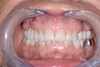

Couronne sur implant